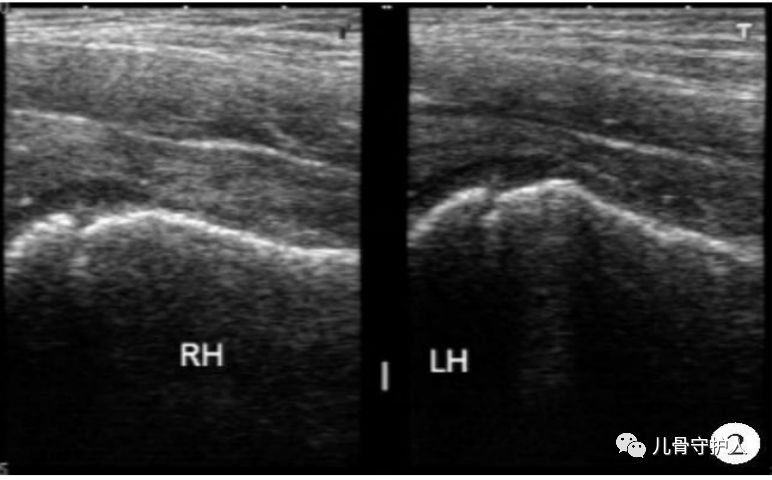

4.X:骨盆轻度倾斜,髋关节囊肿胀,关节间隙增宽,无骨质破坏。B超:患髋股骨颈颈前间隙增宽,双侧差值大于1mm。滑膜增厚,关节积液。